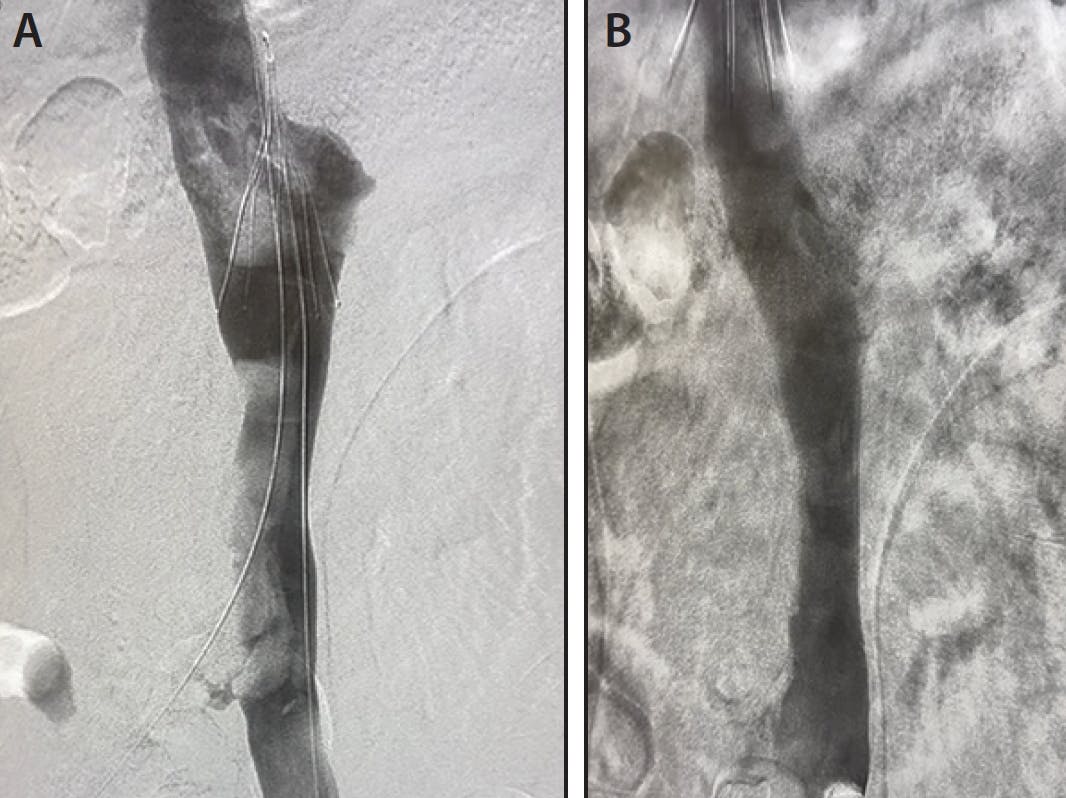

A male in his early 30s presented to the emergency department with extensive swelling in his right leg. A CT scan showed that he had caval atresia and that his collateral caval flow had been obstructed by thrombus extending from the right popliteal vein into his iliac vein (Figure 1A and 1B). With the size of this patient’s veins and amount of clot present, it was determined that the patient would greatly benefit from the use of a larger catheter that could effectively extract a high volume of thrombus. Holding patient safety as the number one priority, it was also decided to keep the access site as small as possible.

Figure 1. Venograms before (A, B) and after (C, D) use of Lightning Flash.

Access was gained in the popliteal and a 16-F, 33-cm DrySeal sheath was placed. With the sheath in place, Lightning Flash was pulled and advanced into the popliteal vein. Once confident the tip of the catheter was at the face of the clot, aspiration was turned on. The catheter was then advanced further into the iliac vein.

As soon as aspiration was activated, a large amount of thrombus was pulled through the tubing and into the cannister. During the entirety of the first pass, Lightning Flash’s clot detection system indicated that the catheter was actively engaging thrombus. On the final pass, the system indicated that the catheter was no longer interacting with clot. Promptly, final angiograms were taken and showed that all thrombus had been removed (Figure 1C and 1D).